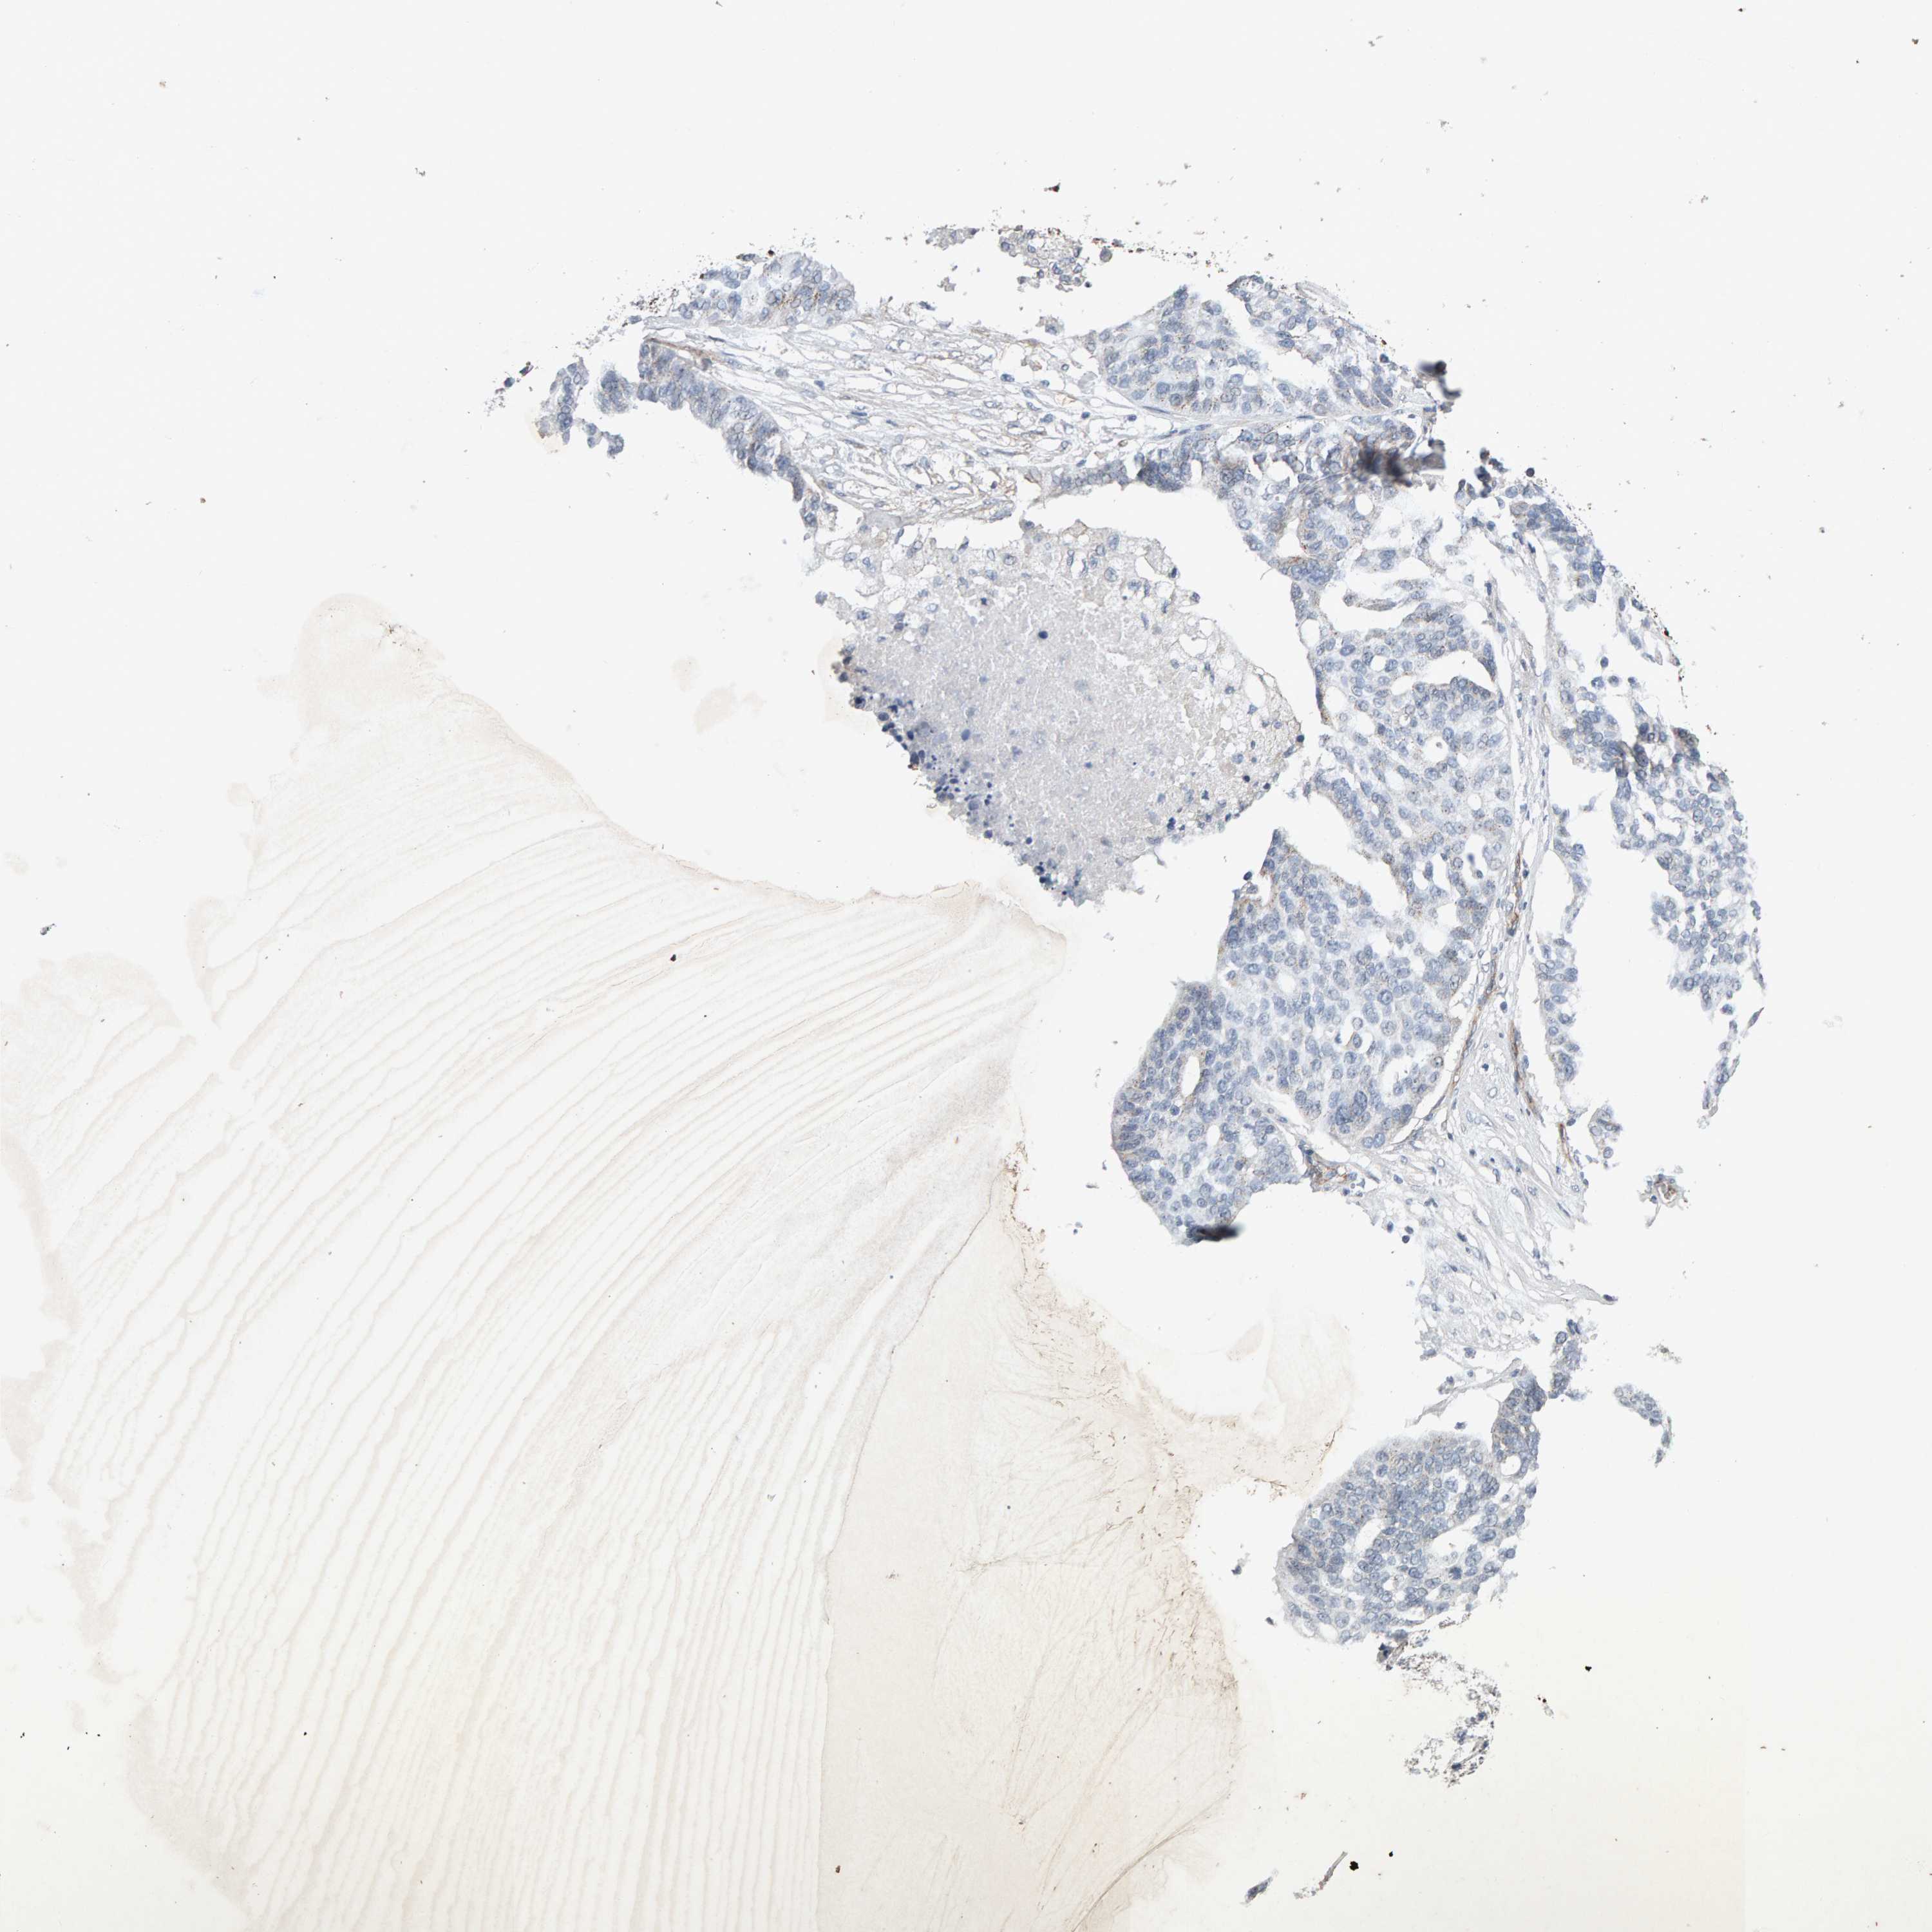

OVARIAN CANCER - Protein expressioni

A mouse-over function shows sample information and annotation data. Click on an image to view it in a full screen mode. Samples can be filtered based on level of antibody staining by selecting one or several of the following categories: high, medium, low and not detected. The assay and annotation is described here.

Note that samples used for immunohistochemistry by the Human Protein Atlas do not correspond to samples in the TCGA dataset.

Antibody stainingi

Antibody staining in the annotated cell types in the current human tissue is reported as not detected, low, medium, or high, based on conventional immunohistochemistry profiling in selected tissues. This score is based on the combination of the staining intensity and fraction of stained cells.

Each image is clickable and will lead to virtual microscopy that enables deeper exploration of all samples and also displays staining intensity scores, fraction scores and subcellular localization as well as patient and tissue information for each sample.

Antibody CAB022442

Antibody CAB022443

Carcinoma, endometroid

Cystadenocarcinoma, serous, NOS

Cystadenocarcinoma, mucinous, NOS

Carcinoma, NOS